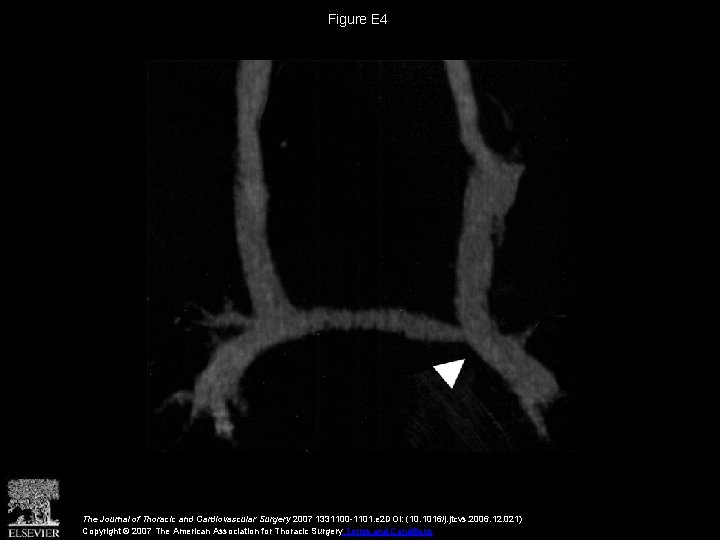

Figure E 4 The Journal of Thoracic and Cardiovascular Surgery 2007 1331100 -1101. e

Figure E 4 The Journal of Thoracic and Cardiovascular Surgery 2007 1331100 -1101. e 2 DOI: (10. 1016/j. jtcvs. 2006. 12. 021) Copyright © 2007 The American Association for Thoracic Surgery Terms and Conditions